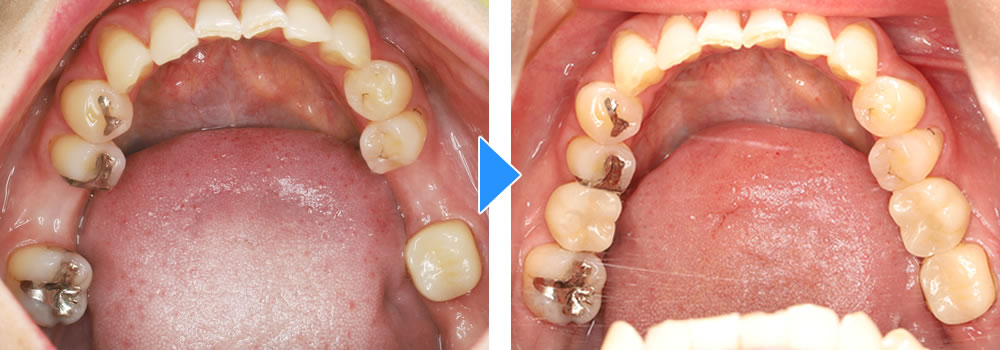

治療前後の比較

治療前後の比較画像です。患者さまにも色合い等大変、満足いただけました。